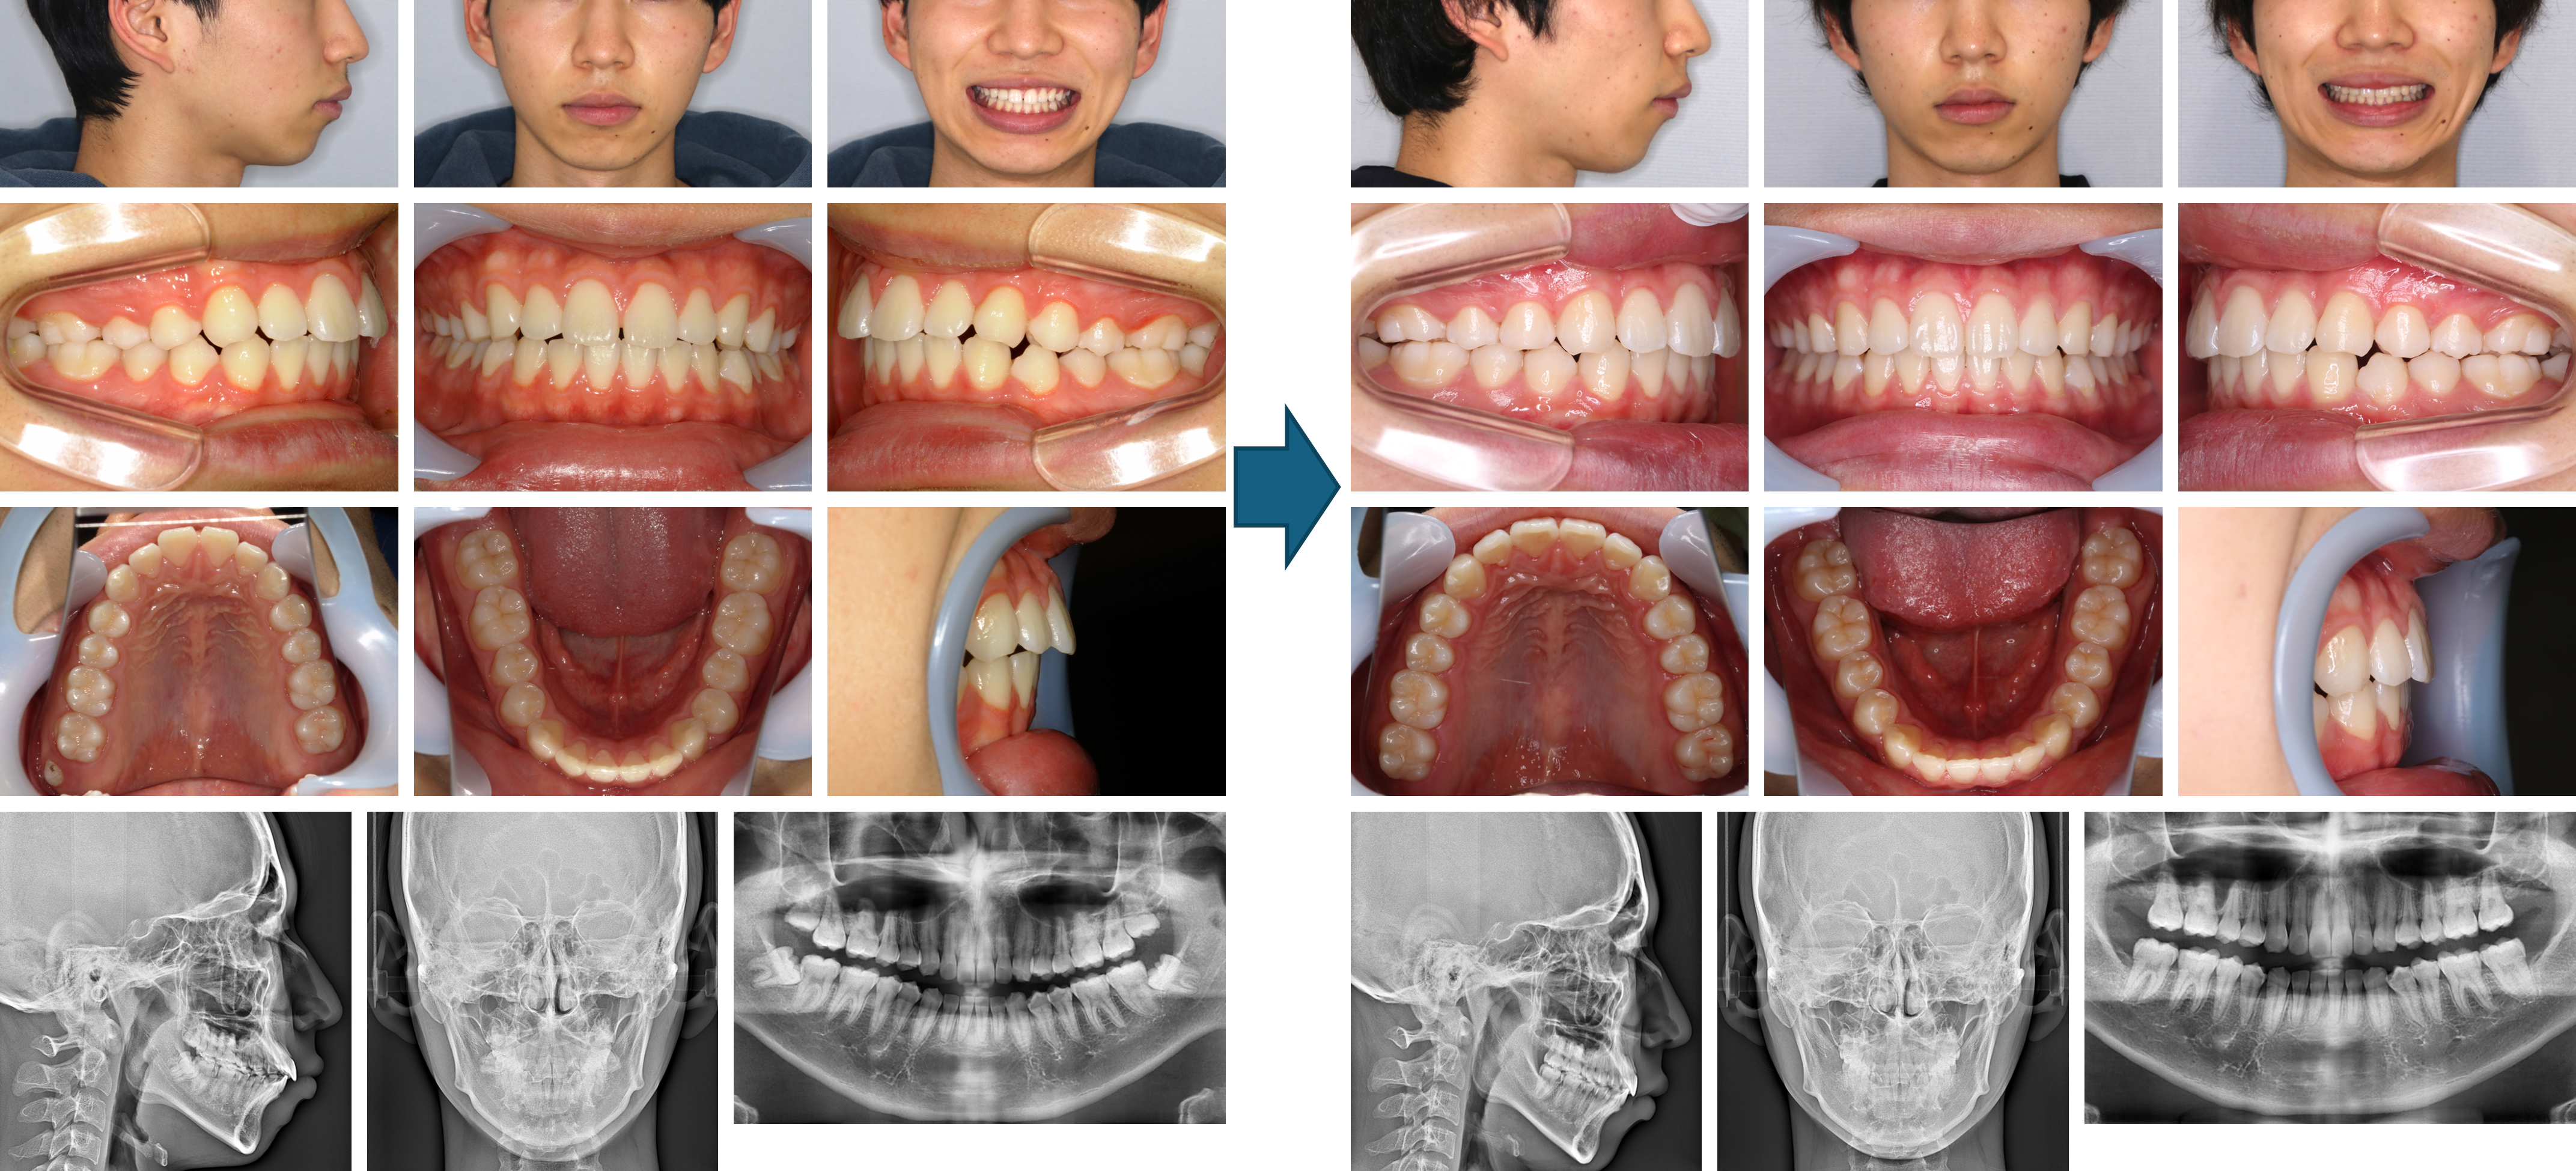

【治療例】初診時年齢:33歳10か月 / 性別:女性 / 主訴:前歯で咬めない

症例の概要:この症例は、下顎右側第一小臼歯に歯牙腫を認めた軽度の開咬症例である。他院では上下第一小臼歯抜歯症例と言われセカンドオピニオンとして当院に来院。当院では上下第三大臼歯抜歯後、歯牙腫に配慮して、マウスピース型(アライナー型)矯正装置(インビザライン®)を用いてIPRを併用しながら小臼歯非抜歯で治療した症例である。

主訴: 前歯で咬めない

診断名: 軽度の開咬を伴う叢生症例

使用した主な装置: マウスピース型(アライナー型)矯正装置(インビザライン®)、IPR、顎間ゴム

抜歯/非抜歯および抜歯部位: 非抜歯

※上記価格は税込価格です。消費税は10%で表示しております。

※こちらの症例は2022年1月から2024年10月に行った矯正です

治療期間:2年9か月

治療回数:20回

リスクの副作用:歯の移動や抜歯による違和感や疼痛、口内炎、歯肉退縮、歯根吸収が生じることがある